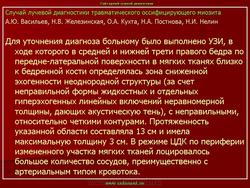

Описывается клинический случай редкого заболевания — оссифицирующего миозита — у девочки 11 лет. Представлены данные литературы, касающиеся этого заболевания.